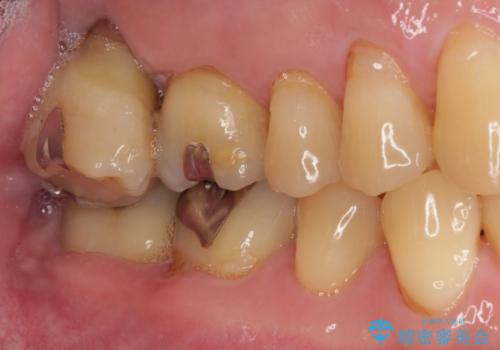

外側に飛び出している歯 部分矯正を用いた奥歯の補綴治療

- 奥歯のむし歯治療を希望して来院された患者様です。

上顎の奥歯は、左右ともに外側に転位しており、特に右上はむし歯の範囲が広く、根管治療も必要な状態でした。

上顎左右の歯をアンカースクリューを用いた部分矯正により位置を修正し、オールセラミッククラウンにて補綴治療を行うこととしました。